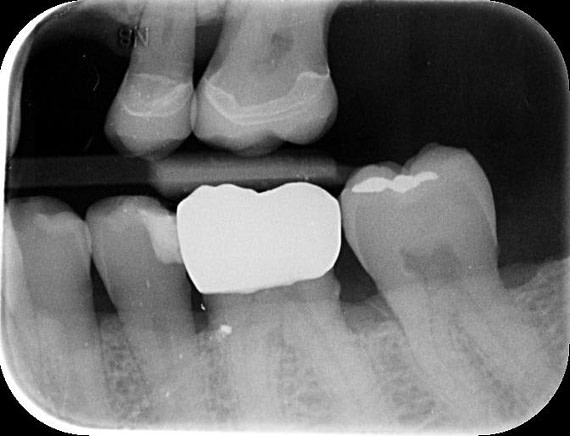

A radiographic assessment confirmed the proper integration and positioning of the implant.

Implant detection matches the scan body in the intraoral scan with the digital library. A colour scale is given to show the accuracy of the matching (Green is good).